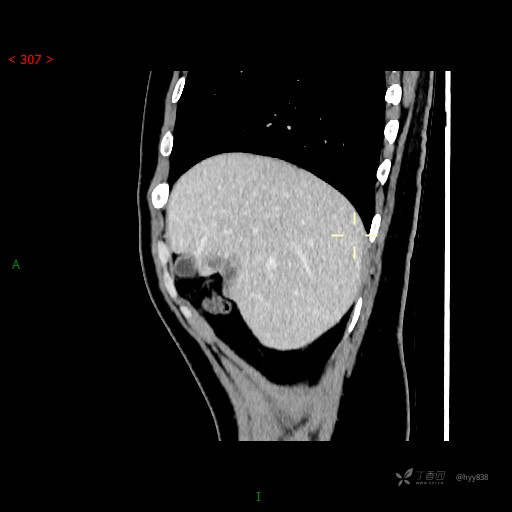

年轻男性,肝脏孤立结节、邻近包膜如此内陷,不知“坑”为何物---(结果公布)

简要病史: 患者1月余出现腰背部疼痛,以夜间疼痛为甚,伴双下肢胀痛,无腹胀、腹痛,无咳嗽、咳痰,无头晕、头痛等症状,门诊超声提示肝结节状占位

临床诊断:肝占位

延迟期